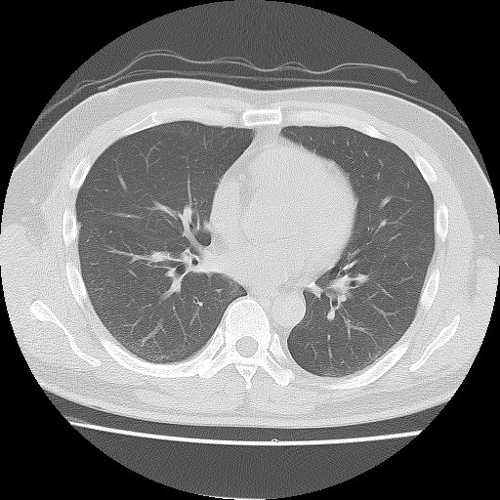

【CT(computed tomography)】

管球(ドーナツ状の部分にあるX線を出す機械)がX線を出しながら体の周りを回転し、人体を透過したX線をコンピューター処理して画像化します。短時間で広い範囲を撮影でき、様々な方向からの画像や3Dを作成します。